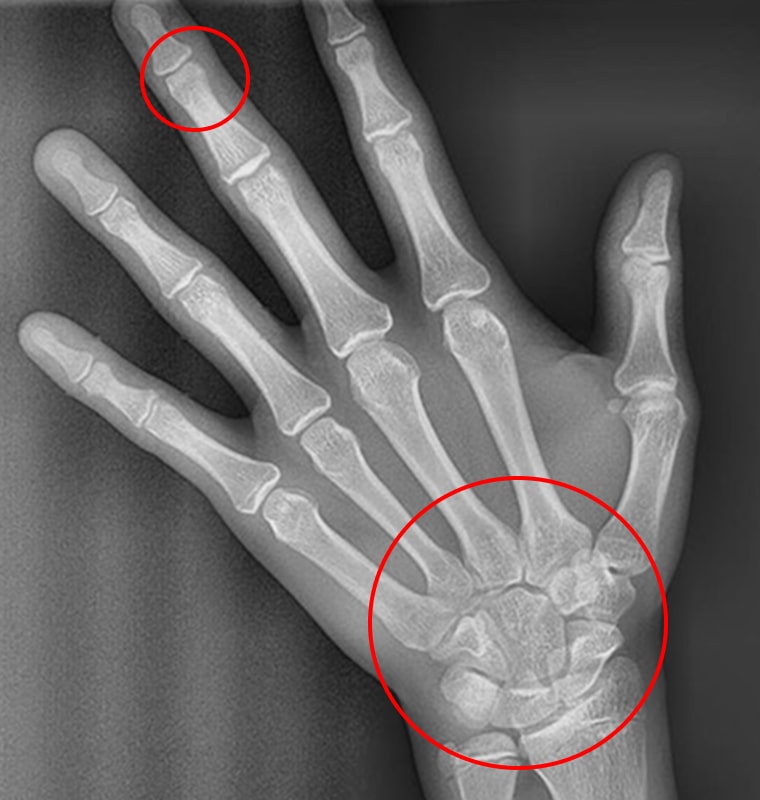

X-RAY 검사를 통한 발육 상태 진단

X-RAY 사진

STEP 01 종자골 미출현

종자골 미출현은 성장이 본격화되기 전의 상태로

초기 교정 및 예방적 치료를 시작하기에 적합한 시기입니다.

이 단계에서 적절한 교정 치료를 진행하면 성장기 동안

발생할 수 있는 심각한 부정교합 문제를 예방하고

이후 치료 효과를 극대화할 수 있습니다.

STEP 02 종자골 출현 + 가운데 손가락 마디뼈 미융합

사춘기 급성장기의 초기 또는 중간 단계를 나타내며

이 시기에 교정 치료를 시작하면 골격 문제와 부정교합을

효과적으로 해결할 수 있습니다.

적절한 시기에 치료를 시작함으로써 성장기 동안

최상의 결과를 얻을 수 있습니다.

STEP 03 손목뼈 미융합 + 가운데 손가락 마디뼈 융합

손목뼈가 미융합 상태이면서 손가락 마디뼈가

융합된 상태는 성장기 후반부를 나타냅니다.

이 시기는 골격 교정보다는 치아 배열과 교합 정리에

중점을 둔 치료가 주로 이루어지며, 남아 있는 소량의

성장 여력을 최대한 활용하는 것이 중요합니다.

STEP 04 손목뼈 융합

손목뼈가 융합된 상태는 골격 성장이 완료된

단계를 의미하며, 더 이상 성장 조정은 불가능합니다.

이 시기에는 치아 배열과 교합 개선을 위한 정교한 교정

치료에 초점을 맞추며, 골격적 문제가 있는 경우 수술적

접근이 필요할 수 있습니다.